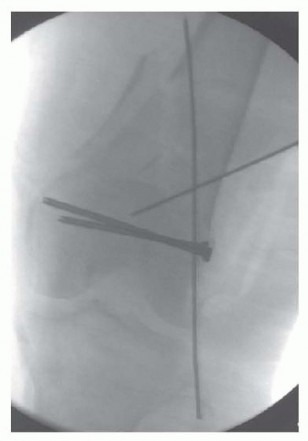

### FIG 15 • A. C-arm view of the uninjured knee with patella-forward facing. B. This is followed by imaging of the ipsilateral hip to obtain the lesser trochanter profile (outlined). A similar profile should be recreated on the injured side with the hip bum C. Positioning of the C-arm relative to the flexed knee to obtain a notch view to evaluate for guide pin penetration in the posterior aspect. D. The resulting C-arm image. A notch view is useful for screw trajectories in the distal femur. This is achieved by the C-arm angled roughly around 30 to 45 degrees directed cephalad and visualization will depend on the concurrent amount of knee flexion ( FIG 15C,D). ## Approach The best-known approach for the treatment of distal femur fractures has been the straight lateral approach ( FIG 16). This is suitable for all fracture types, mostly types A and C1. The incision may curve distally toward the tibial tubercle, and osteotomy may be performed. Newer approaches include a lateral inverted U to allow better access to the joint and to allow for plate placement. The minimally invasive lateral approach can be used for certain fractures and implants. The joint must be visualized, reduced, and stabilized. The placement of the plate on the shaft is done submuscularly, and reduction and fixation are done percutaneously under fluoroscopic guidance. This is ideal for the LISS plate or plating system with targeting devices for the screws in the plate. A modified anterior approach (the swashbuckler) has been described by Starr et al. 16 This involves a midline incision. A lateral parapatellar arthrotomy is done with elevation of the vastus lateralis as in the lateral approach.

### TECH FIG 4 • The condyles are reduced under direct visualization (A) and confirmed with AP (B) and lateral (C) intraoperative fluoroscopic images. D. Guide pins through the plate template or screw trajectory guide are used to temporarily stabilize the intercondylar split. - Definitive Fixation of the Condyles This can be accomplished outside the plate first and supplemented with screws through the plate. The area around the proposed plate, the “periphery,” can be used for the screw placement to avoid interference with the plate placement itself. If this is done, then the metaphyseal fracture does not necessarily have to be properly reduced before initial screw placement. Screws can also be placed from medial to lateral to avoid interference with the plate. Definitive fixation can be accomplished through the plate also (see next section on Screw Placement). If this is done, the metaphyseal component should be reduced to ensure the proper flexion-extension alignment of the shaft with the condyles. This will ensure that the plate is collinear with the shaft once fixed to the distal segment. Otherwise, a malreduction in the sagittal plane will occur. The temporary Kirschner wires can be left in place to stabilize the joint. ### Reduction of the Shaft to the Distal Segment Once the articular surface is temporarily stabilized or reduced, the reduction of the shaft to the distal segment should be performed before plate application. This can be temporarily stabilized with Kirschner wires or Steinmann pins. Alternatively, precisely placed bumps underneath the distal segment can be used to correct the extension of the distal segment and align it with the shaft. Adjustment or loosening of the temporary external fixator can aid in reduction if needed. The plate can then be placed submuscularly. ### Placement of the Plate Each fixed-angle plating system is designed to help reestablish the valgus alignment of the distal femur. The screws in the distal portion of the plate are designed to be parallel to the joint surface. Thus, the initial guidewires for these screws should be placed parallel and confirmed by fluoroscopy. A distal “joint wire” can be placed to better evaluate this ( TECH FIG 5A). Placing the distal screws parallel to the joint will help ensure that when the shaft is brought to the plate, the anatomic axis of the femur is restored. With the variable-angle locking plates, the same technique should be employed to ensure that the plate is applied in a way to restore the anatomic axis of the femur. A fixedangle central screw hole still exists in these plates to aid in plate application ( FIG 11C, parallel lines; FIG 11D, red arrow/red circle). A distal screw trajectory guide is provided for some systems ( TECH FIG 5B). This can be used to help ensure accurate placement of the plate distally, and initial guidewires can be placed through this. Once the wires are placed, the guide can be removed and replaced with the plate using the wires as a guide. However, the shaft portion of the plate requires submuscular insertion, and thus the plate cannot be brought to an appropriate position to allow this to occur. 482

### TECH FIG 5 • A. Distal reference pin is placed to ensure that the proximal pin is parallel to the joint. B. Clinical picture depicting the guide. C. Different patient showing the penetration of the medial side with the guidewires to allow plate placement. D,E. The plate is placed with additional guide pins in place. - F,G. Lateral intraoperative fluoroscopic images ensure proper plate placement on the femur before screw insertion. To solve this, the guidewires can be driven through the medial side of the knee, which is distal enough to be safe ( TECH FIG 5C). The plate can then be inserted submuscularly and the guidewires driven back through the plate laterally, thus aligning the plate to the distal segment and ensuring proper screw trajectory and plate placement ( TECH FIG 5D,E). A single guidewire in a central hole will still allow flexion-extension placement of the plate if this needs to be adjusted. After placing the initial guidewire parallel to the joint distally, and ensuring the fracture is reduced, the surgeon should obtain fluoroscopic visualization of the plate proximally on the shaft to ensure that the plate is on the bone ( TECH FIG 5F,G). To ensure placement of the plate on the bone both proximally and distally, it is best to stabilize the plate distally 483 (where exposure is) using a guidewire in the center hole. This allows for a pivot point around which the AP positioning of the plate can be manipulated for the shaft. Fluoroscopy to image the lateral is then used to ensure placement.

--- TECH FIG 6 • A,B. Patient seen in FIG 15C,D, with the guidewire now pulled back and an appropriately sized screw placed. Once the AP position is obtained, the plate is stabilized proximally. The plate should be temporarily stabilized to the bone proximally. Before the temporary stabilization, the length and rotation must be checked. Ideally, if the temporary fixator is in place, these two parameters have been maintained during the course of the operation. If no screw targeting guide is present, a percutaneous provisional fixation pin can be used to stabilize the plate. If a targeting guide is used, then a soft tissue guide for the most proximal hole is placed percutaneously and a drill bit or guidewire is used to stabilize the plate. The variable-angle locking plates also have proximal shaft targeting devices; however, variable locking trajectories can only be accomplished outside the targeting device and can be cumbersome. Generally, variable-angle locking is not necessary in the shaft and locking screws collinear with the hole can be placed through the targeting device. ( FIG 11E, red arrows showing perpendicular nature of locking screws; FIG 11F, variable-angle locking screws in the shaft are useful in cases where there is a preexisting hip replacement with a femoral component.) Again, the flexion-extension reduction should be checked. This procedure creates our “box” construct, which aids in the placement of screws through the targeting device (if used) and in temporary stabilization of the fracture construct. ### Screw Placement If the intercondylar split is going to be stabilized by screws through the plate, partially threaded screws or overdrilled fully threaded screws should be used first to provide interfragmentary compression. Specially designed conical screws for certain systems exist, or large partially threaded screws can be used ( >4.5 mm). This also compresses the plate to the bone. Once the articular injury is addressed, at least two additional locking screws should be placed into the distal segment to secure the plate and the alignment. The trajectory of distal locking screws can be assessed on the notch view to ensure that penetration through the intercondylar notch does not occur ( TECH FIG 6; see FIG 15C for C-arm setup and position for this image). Before placing the locking screws, the length, rotation, and alignment must be checked again if no fixator or distractor is in place holding the fracture alignment. The plate can be locked to the distal segment and then used to manipulate the distal segment relative to the shaft for the flexion-extension reduction. This, however, is predicated on proper distal alignment of the plate. Otherwise, once the plate is fixed to the distal segment in a malposition and the fracture reduced, the plate may be anterior or posterior on the shaft. The distal screws in a variable-angle locking plate are noncircular to allow for the variable-angle locking mechanism. Screws can be placed directly collinear or with a “variability” of 15 degrees in any direction depending on the system used (see FIG 11D, square outline). ### Attaching the Distal Segment to the Shaft The distal segment is now fixed and can be attached to the shaft. If there is malalignment in the coronal plane but the sagittal plane alignment is reduced, the shaft can be “pulled” to the plate by means of various threaded devices or a nonlocking screw that can be placed freehand under fluoroscopic guidance or through a targeting jig ( TECH FIG 7). ### Placement of Additional Screws Once proper reduction of the fracture is temporarily achieved and the plate is in proper position, additional screws can be placed. If the targeting screw guide is used, percutaneous locking screws can be placed through the soft tissue drill or screw guides ( TECH FIG 8A-C). If no targeting guide is available, fluoroscopic guidance and a percutaneous method can be used freehand. 484